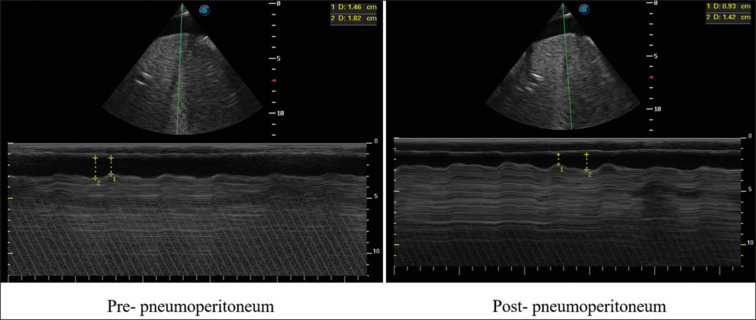

Background: The establishment of pneumoperitoneum has impacts on patient's cardiovascular function. In this study, the respiratory variation of inferior vena cava (IVC), stroke volume (SV) index, and other parameters was monitored to determine how the pneumoperitoneum affects the patient's hemodynamic and acknowledge how to resolve it.

Materials and methods: Fifty-five patients were randomly divided into Group A (8 mmHg), Group B (10 mmHg), Group C (12 mmHg), Group D (14 mmHg), and Group E (12 mmHg, infusion with 7 mL/kg crystalloid solution). The parameters including IVC variability, SV index, mean artery pressure (MAP), heart rate (HR), cardiac output index (CI), and airway pressure were measured, to compare the changes before and after pneumoperitoneum.

Results: Among Group A, Group B, Group C, and Group D, there were no significant differences in patients' prepneumoperitoneum information. Compare with prepneumoperitoneum, the difference in IVC variability, SV index, MAP, HR, CI, and airway pressure was statistically significant (P < 0.05). After the establishment of pneumoperitoneum, the difference in IVC variability, SV index, and airway pressure among Group A, Group B, Group C, and Group D was statistically significant (P < 0.05). Compare with Group C, the change rates of IVC variability, SV index, MAP, HR, and CI were smaller in Group E (P < 0.05).

Conclusion: The establishment of pneumoperitoneum could increase the patient's IVC variability and reduce SV index, and with the increase of pressure, IVC variability had an increasing trend, SV index had a decreasing trend. Fluid transfusion could reduce the relative influence of the pneumoperitoneum.